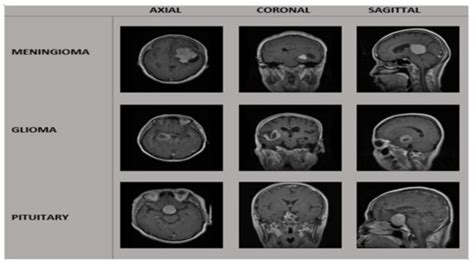

A Hybrid Deep Learning-Based Approach for Brain Tumor Classification